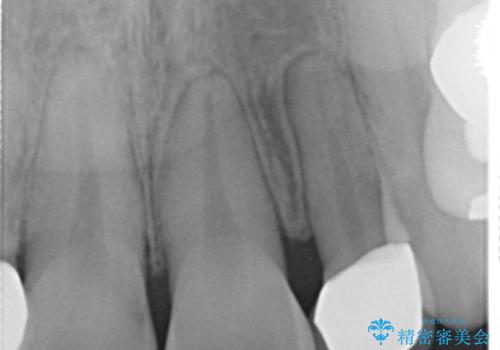

矮小歯 セラミッククラウンで綺麗に 30代女性

全顎的に歯並びにがたつきがあり、上の側切歯(上顎両側2)は生まれつき小さい歯(矮小歯)でした。

矯正治療後、矮小歯をセラミッククラウンにより理想的な歯の大きさに仕上げました。

クラウンの種類:オールセラミッククラウン スペシャル